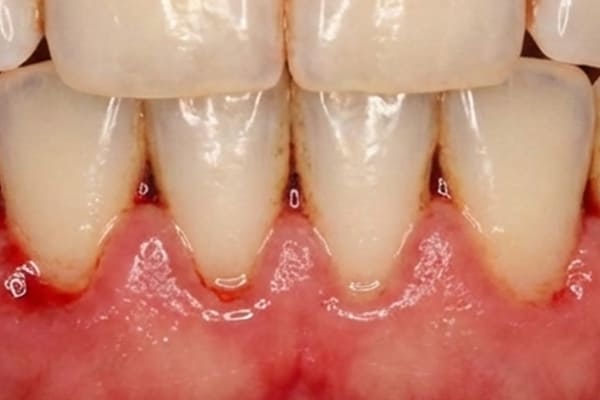

中度歯周炎 危険度★★★

中程度の歯周炎になると、口臭がおこり、歯茎が化膿します。ブラッシングをした際に膿がでることもあります。

歯周ポケットは4~5mm程度です。

この段階での治療法はスケーリングなどを使用して治療をしますが、歯周ポケットが5

mm以上深くなるとフラップ手術をする場合があります。フラップ手術は局所麻酔後、歯茎を切開し、隠れているプラークや歯石を取り除き、歯周病の進行を止める手術を行うことがあります。